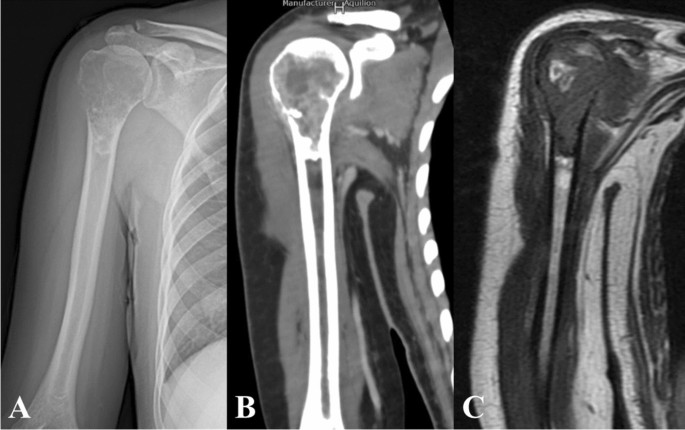

A Clinical Picture At The Time Of Presentation To Emergency B Download Scientific Diagram

A Clinical Picture At The Time Of Presentation To Emergency B Download Scientific Diagram from www.researchgate.net